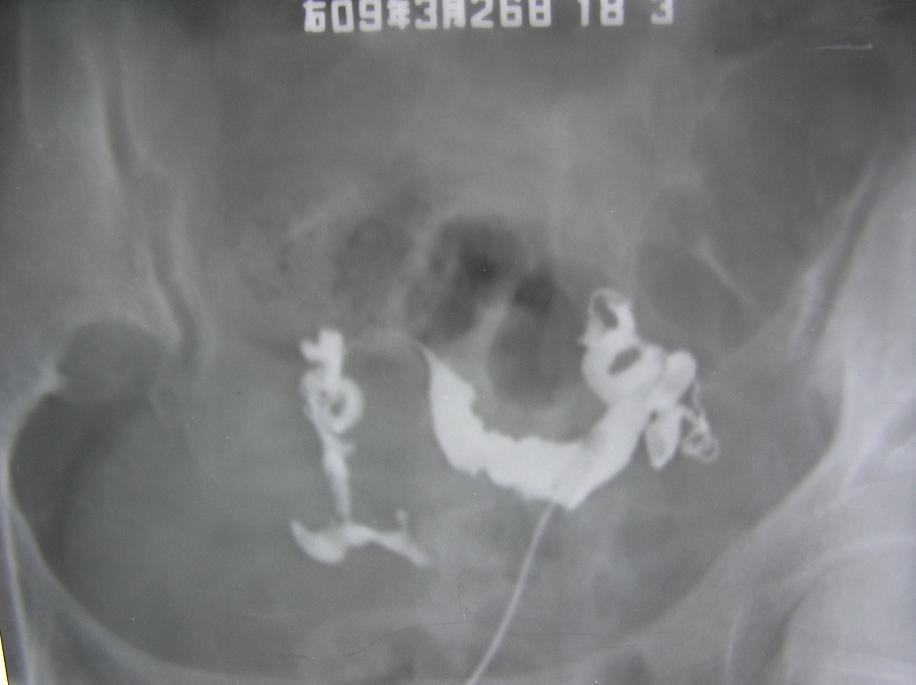

以下是引用杀毒软件在2009-3-27 18:22:00的发言:[br]比较严重的---宫腔粘连,整个宫腔看起来似---双角子宫,弥散像造影剂多在宫旁及输卵管旁,右侧输卵管僵直,壁上有小突起。[br][br]首选考虑----双侧慢性输卵管炎----〔宫腔粘连,输卵管周围粘连〕。 病人应该有很重盆腔炎。[br][br]因为单纯宫腔粘连,输卵管表现可保持正常,但此例子宫及输卵管都有明显改变的表现----不能排除---结核,建议---ppd。[br]

以下是引用随光逐影在2009-3-28 7:59:00的发言:[br]考虑为:1)鞍形子宫。2)宫腔炎。3)双侧慢性输卵管炎。